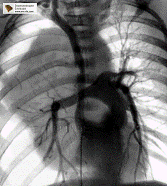

рентгено-контрастное вещество.Особым разделом специализированной

рентгенодиагностики являются различные виды ангиографии и лимфографии,

показывающие полный или частичный «блок» для прохождения контрастного вещества

в зоне злокачественной опухоли или метастатически пораженного лимфатического

узла.

Холицистография

Маммография ЭРПХГ

Почечная ангиография Лимфография